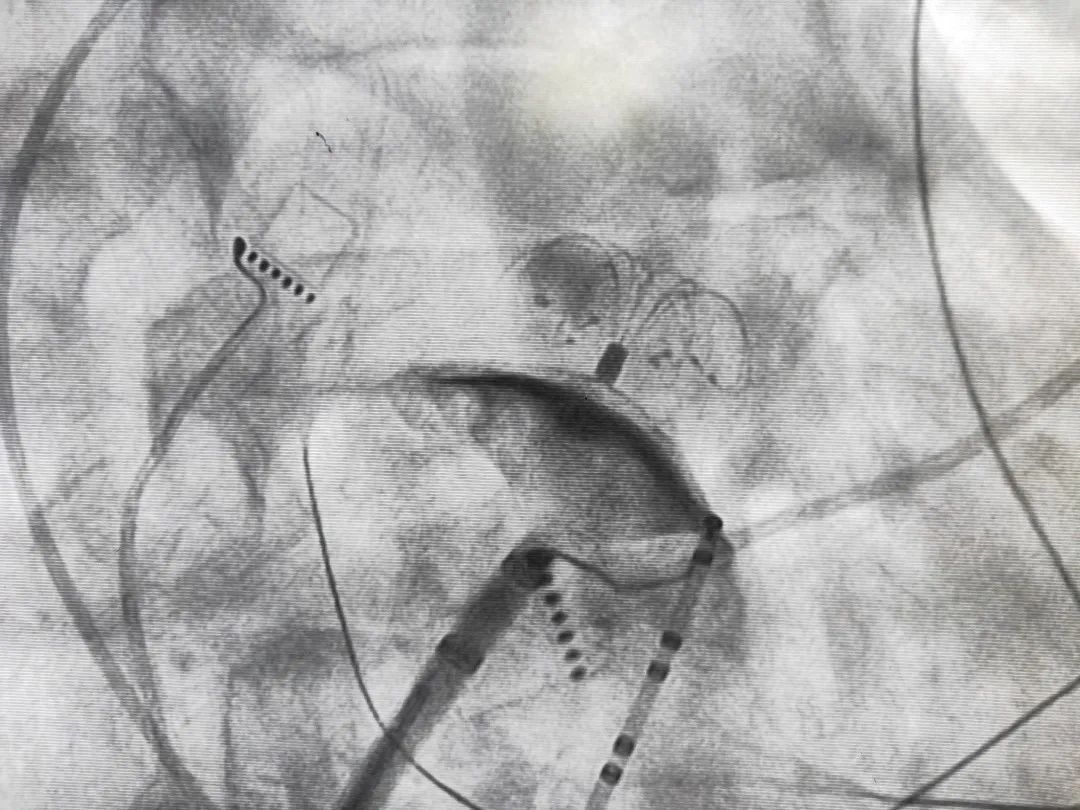

左心耳封堵手术过程大约1小时,心内科医生会在血管造影及超声引导下,在患者大腿内侧的股静脉伸入导管,穿刺房 间隔,将左心耳封堵器输送到左心耳并植入。左心耳封堵器好像一把伞固定在左心耳入口,形成一道屏障, 避免血液进入左心耳形成血块。